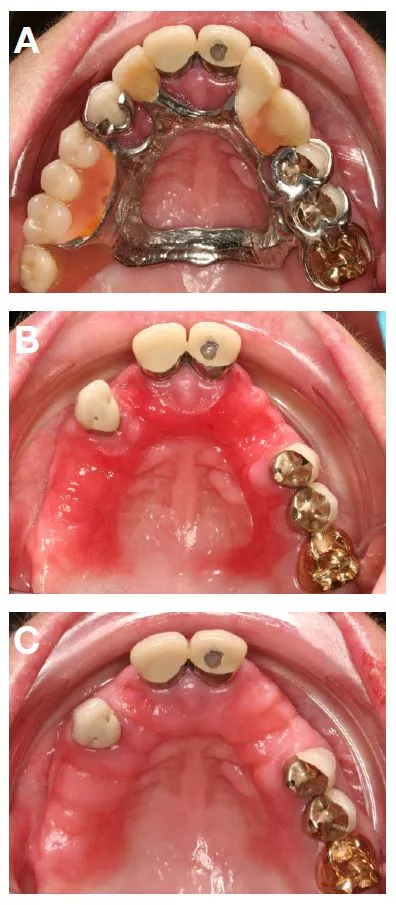

Tabelle 5 zeigt alle relevanten mechanischen Irritationen, wobei unzureichender Randschluss von FZ (7,7%), unzureichender Halt von HZ (5,0%) oder Schaukeln von HZ bei Druckbelastung (4,3%) am häufigsten festgestellt wurden. Abbildung 3 zeigt klinische Beispiele für relevante mechanische Irritationen durch FZ und HZ.

Mechanische Irritationen

Von den 95 Patienten (15,2% der 625 Patienten), die relevante mechanische Irritationen durch FZ und HZ aufwiesen, hatten 28 (29,5%) keine andere relevante zahnmedizinische oder orofaziale Diagnose, während 67 (70,5%) mindestens eine andere relevante dentale oder orofaziale Diagnose aufwiesen (meist funktionelle Symptome, plaquebezogene Symptome und Verarbeitungsfehler).